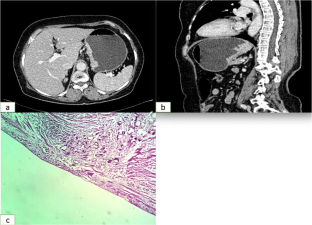

Fig. 2